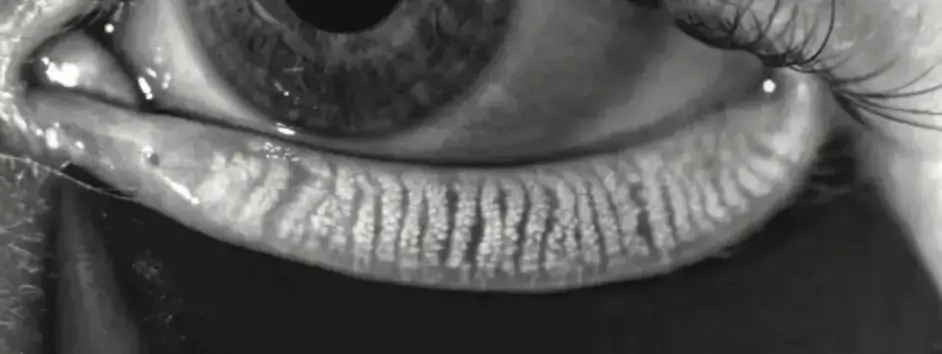

Si cela vous semble familier, le problème n'est probablement pas le manque de larmes, mais leur qualité. Le DGM se produit lorsque les glandes sébacées de vos paupières se bloquent, provoquant une évaporation rapide des larmes. Ignoré, le DGM peut mener à une perte permanente des glandes (atrophie) et à une sécheresse oculaire chronique irréversible.

Comprendre le dysfonctionnement des glandes de Meibomius (DGM) est la première étape pour restaurer la qualité de vos larmes et retrouver un confort oculaire durable. Loin d'être un problème isolé, cette condition est la cause numéro un de la sécheresse oculaire et est intimement liée à l'inflammation des paupières, comme la blépharite ou la rosacée oculaire, qui en sont souvent à la fois la cause et la conséquence.

Plusieurs facteurs peuvent déclencher ou aggraver un DGM. L'âge et les changements hormonaux, notamment la ménopause, jouent un rôle majeur. Le port prolongé de lentilles de contact peut également nuire à la fonction des glandes, tout comme la prise de certains médicaments, un effet connu de la sécheresse oculaire post-Accutane. À la Clinique CARE, notre processus de diagnostic par imagerie de pointe (meibographie) permet d'évaluer précisément l'état de vos glandes pour cibler la véritable source de votre inconfort.